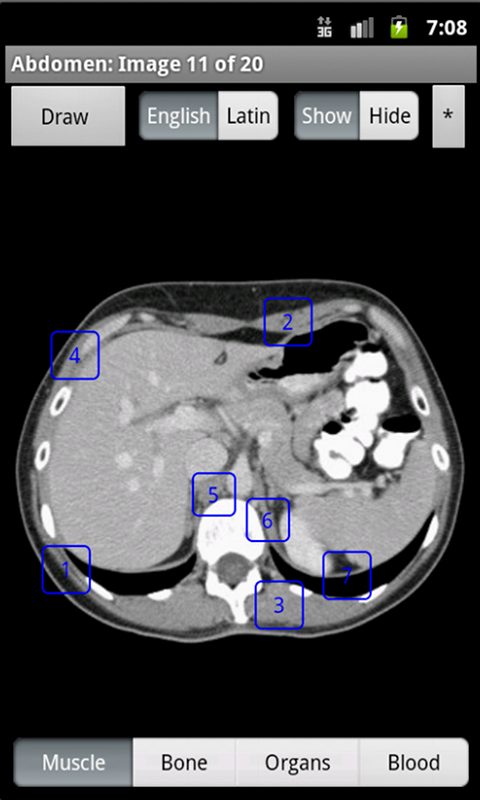

Learning anatomy interactively with a touchscreen device is dynamic and engaging. Having it as an app, makes the information available anywhere, anytime. Using the Samsung Pen, doctors can go over anatomy with patients, annotate normal anatomy images, and send the patient an email of the annotated image. This is a revolutionary way to increase doctor patient communication. iAnatomy is an exciting electronic anatomy atlas. The images are interactive. If a label is touched, the name of the structure is shown. Images span from the face to the pelvis. The face and neck images and the female pelvis images are reconstructed from data from the National Library of Medicine's Visible Human ProjectⓇ. iAnatomy is designed to stand on its own and does not require an ongoing internet connection. Anatomy labels can be hidden or shown. Anatomy can be viewed with either English or Latin medical terminology. A 'Draw' option allows the user to take an image, annotate it and mark it up and then save and/or email the annotated image. This is useful for healthcare workers using the image annotation to explain relevant anatomy and pathology to their patients. They can then email the image with their notations to the patient. This will help improve communication between patients and healthcare workers and is a useful tool for patient education.

iAnatomy helps students from middle school through medical school learn anatomy in a fun, organized way. You first choose the body part you want to study, then pick the category of anatomy labels to be displayed. The labels are divided into Muscle, Bone, Organs, or Blood categories in order to focus learning and limit the number of labels on the image at any one time.